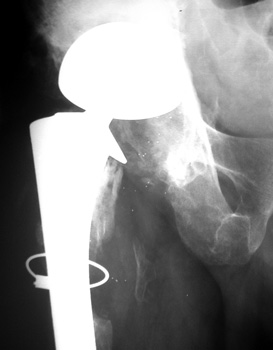

No prior studies available. Abnormally widened interfaces surrounding entire cement mantle of femoral component, consistent with loosening.

LOOSENING